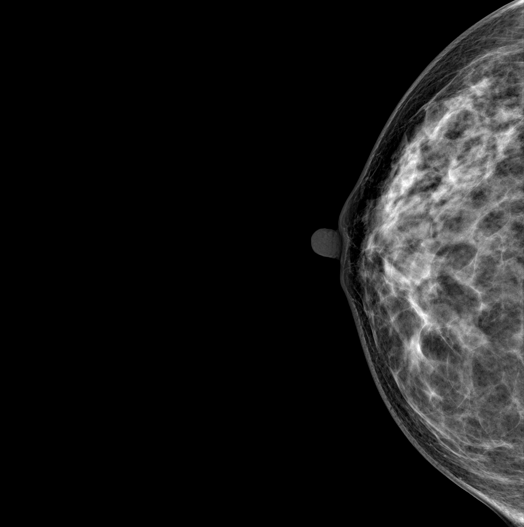

DBT (Digital Breast Tomosynthesis)

The X-ray tube moves on the breast and takes high-definition, high-resolution images with high contrast from various angles.

The images are reconstructed in 3D TO Provide accurate information about the location and condition of the lesion